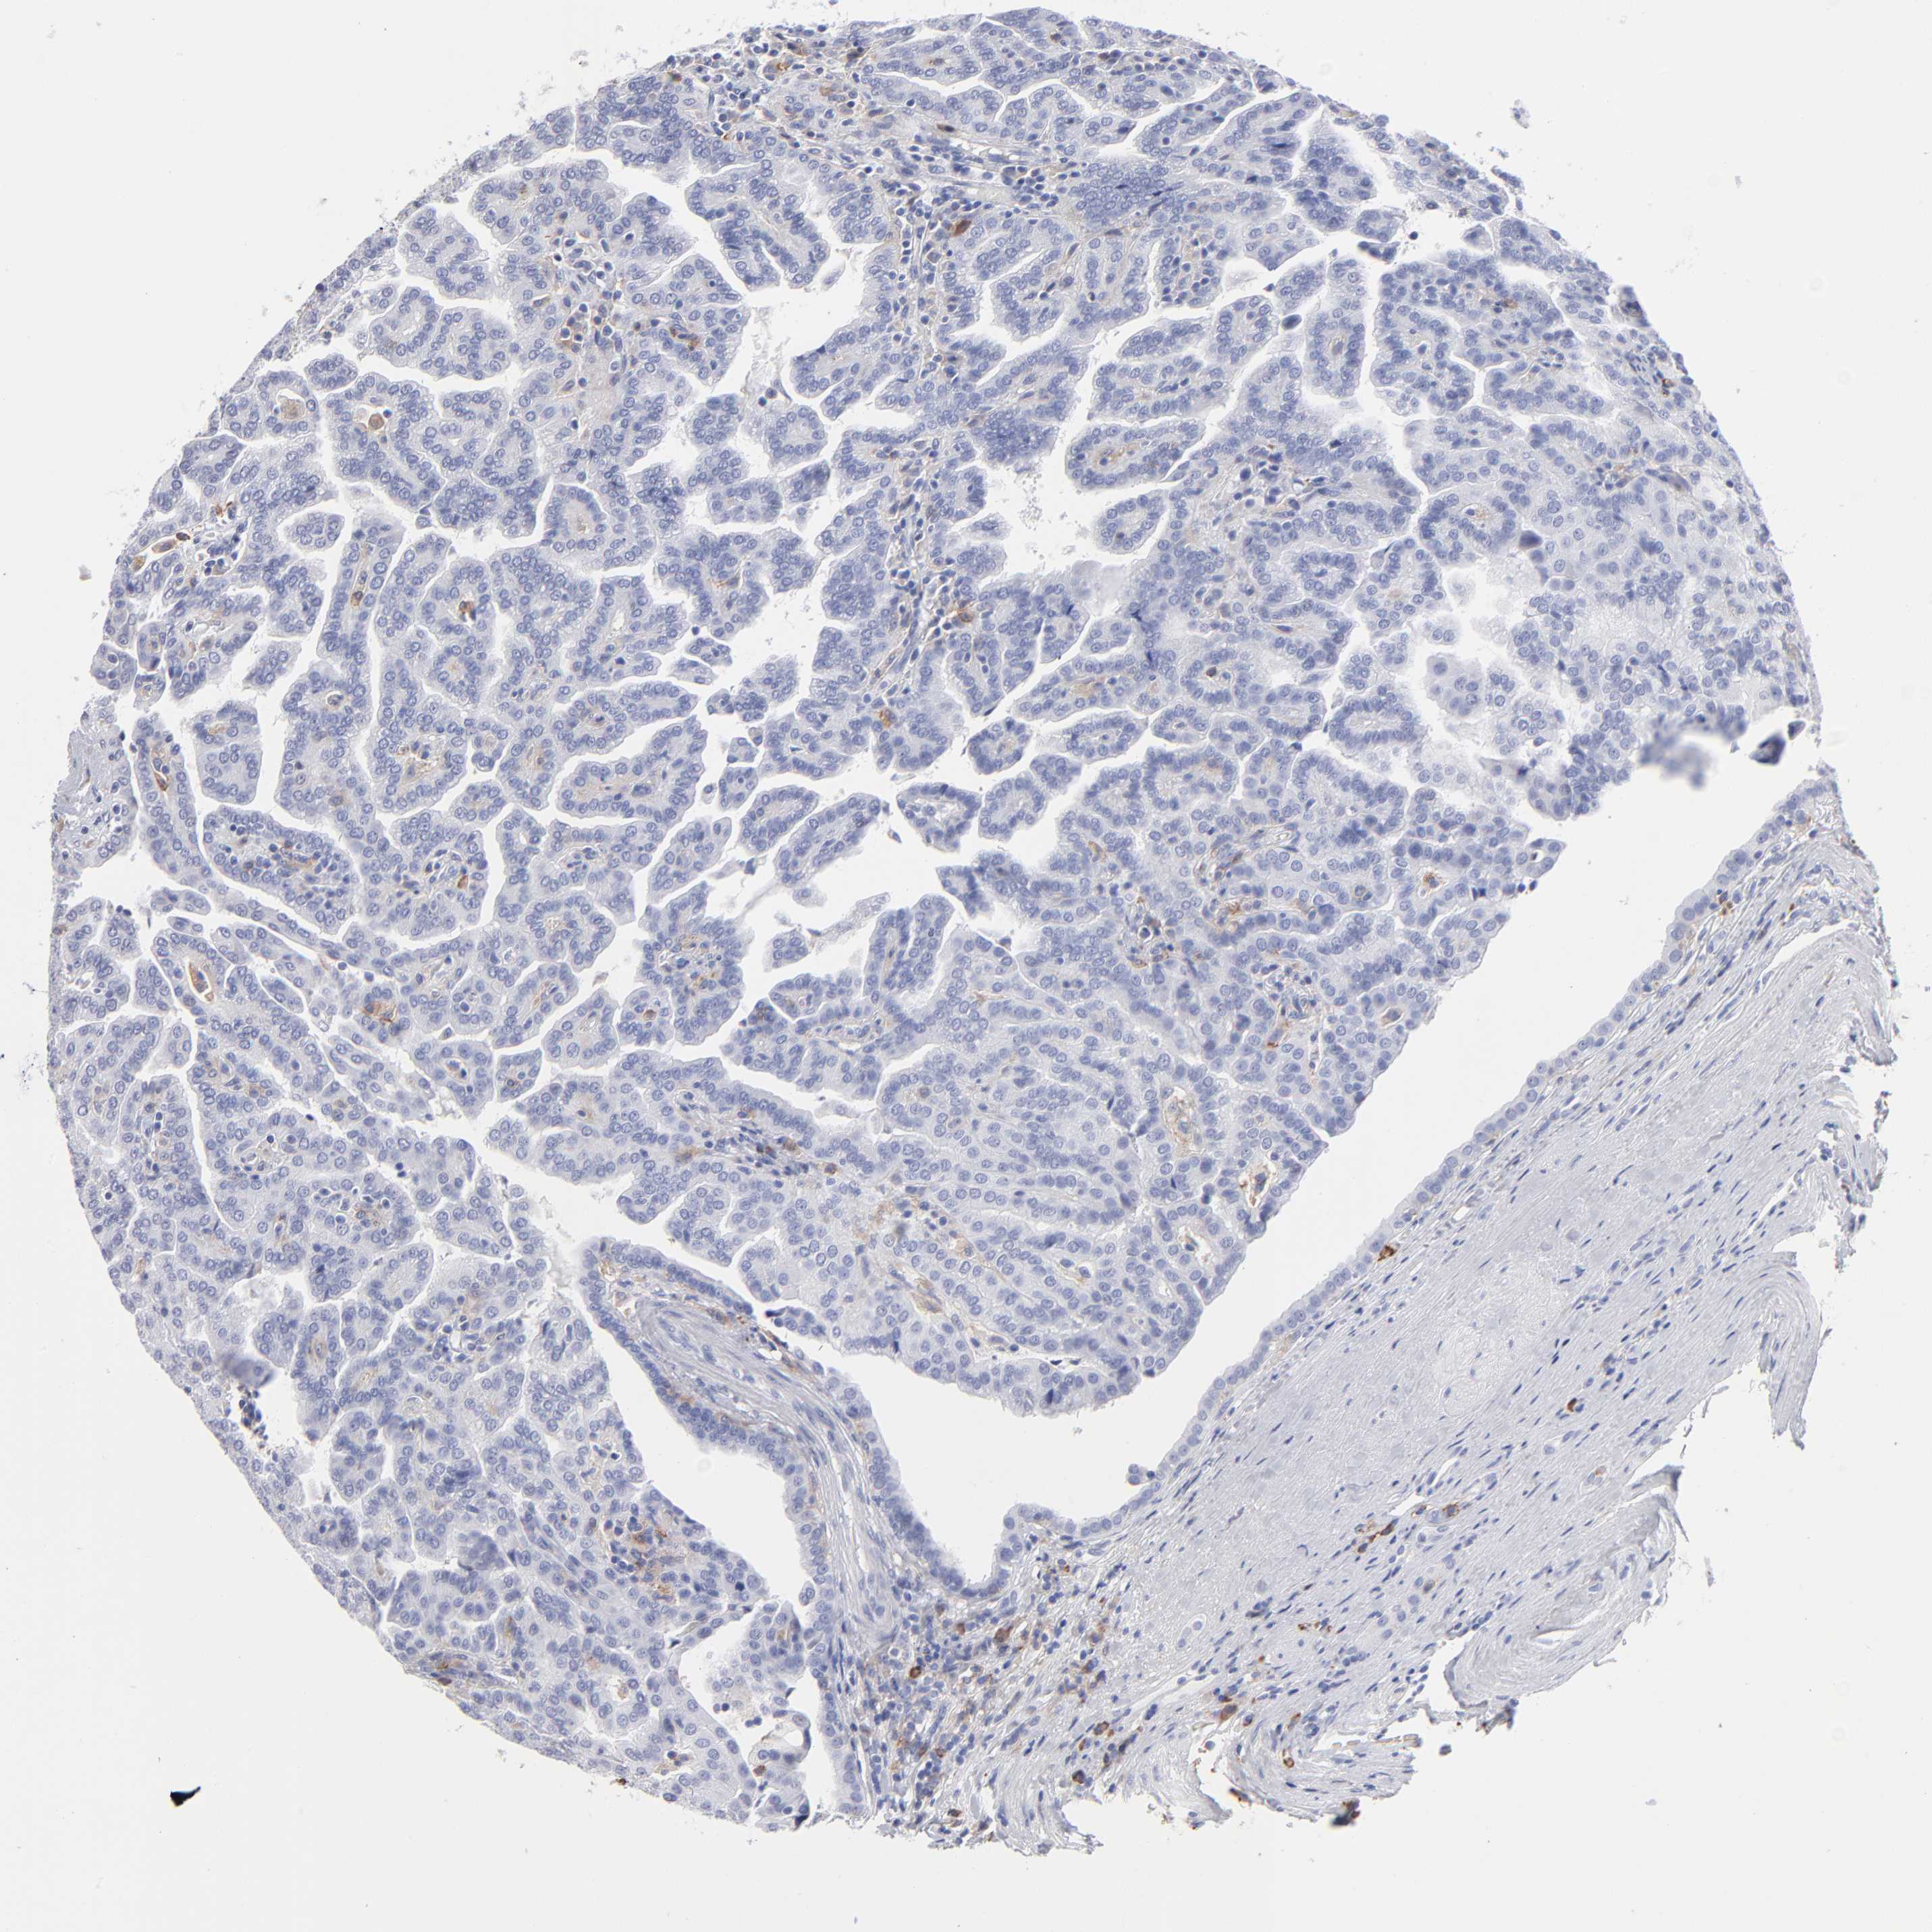

Renal cancer

Kidney renal papillary cell carcinoma